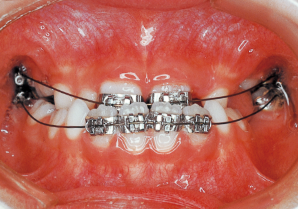

7 1-22-’80 Beginning of first phase

8 1-20-’81 One year after start of treatment

9 7-28-’82 After Phase 1 Treatment 11 years old

Aware that treatment would be challenging, we proceeded with the first phase of treatment based on the current functional status and anticipated developmental implications (7). During the mixed dentition phase, the body responds readily to treatment, allowing for relatively rapid tooth movement and changes in jaw position (8,9). Subsequently, once freed from mechanical stimulation, growth continues according to inherent predispositions, often appearing to disregard occlusal functional efficiency (10,11). These changes are clearly observable on cephalometric radiographs (12). After confirming the extent and direction of growth, we decided to incorporate surgical intervention into the treatment plan and wait until the age when growth begin to decline.